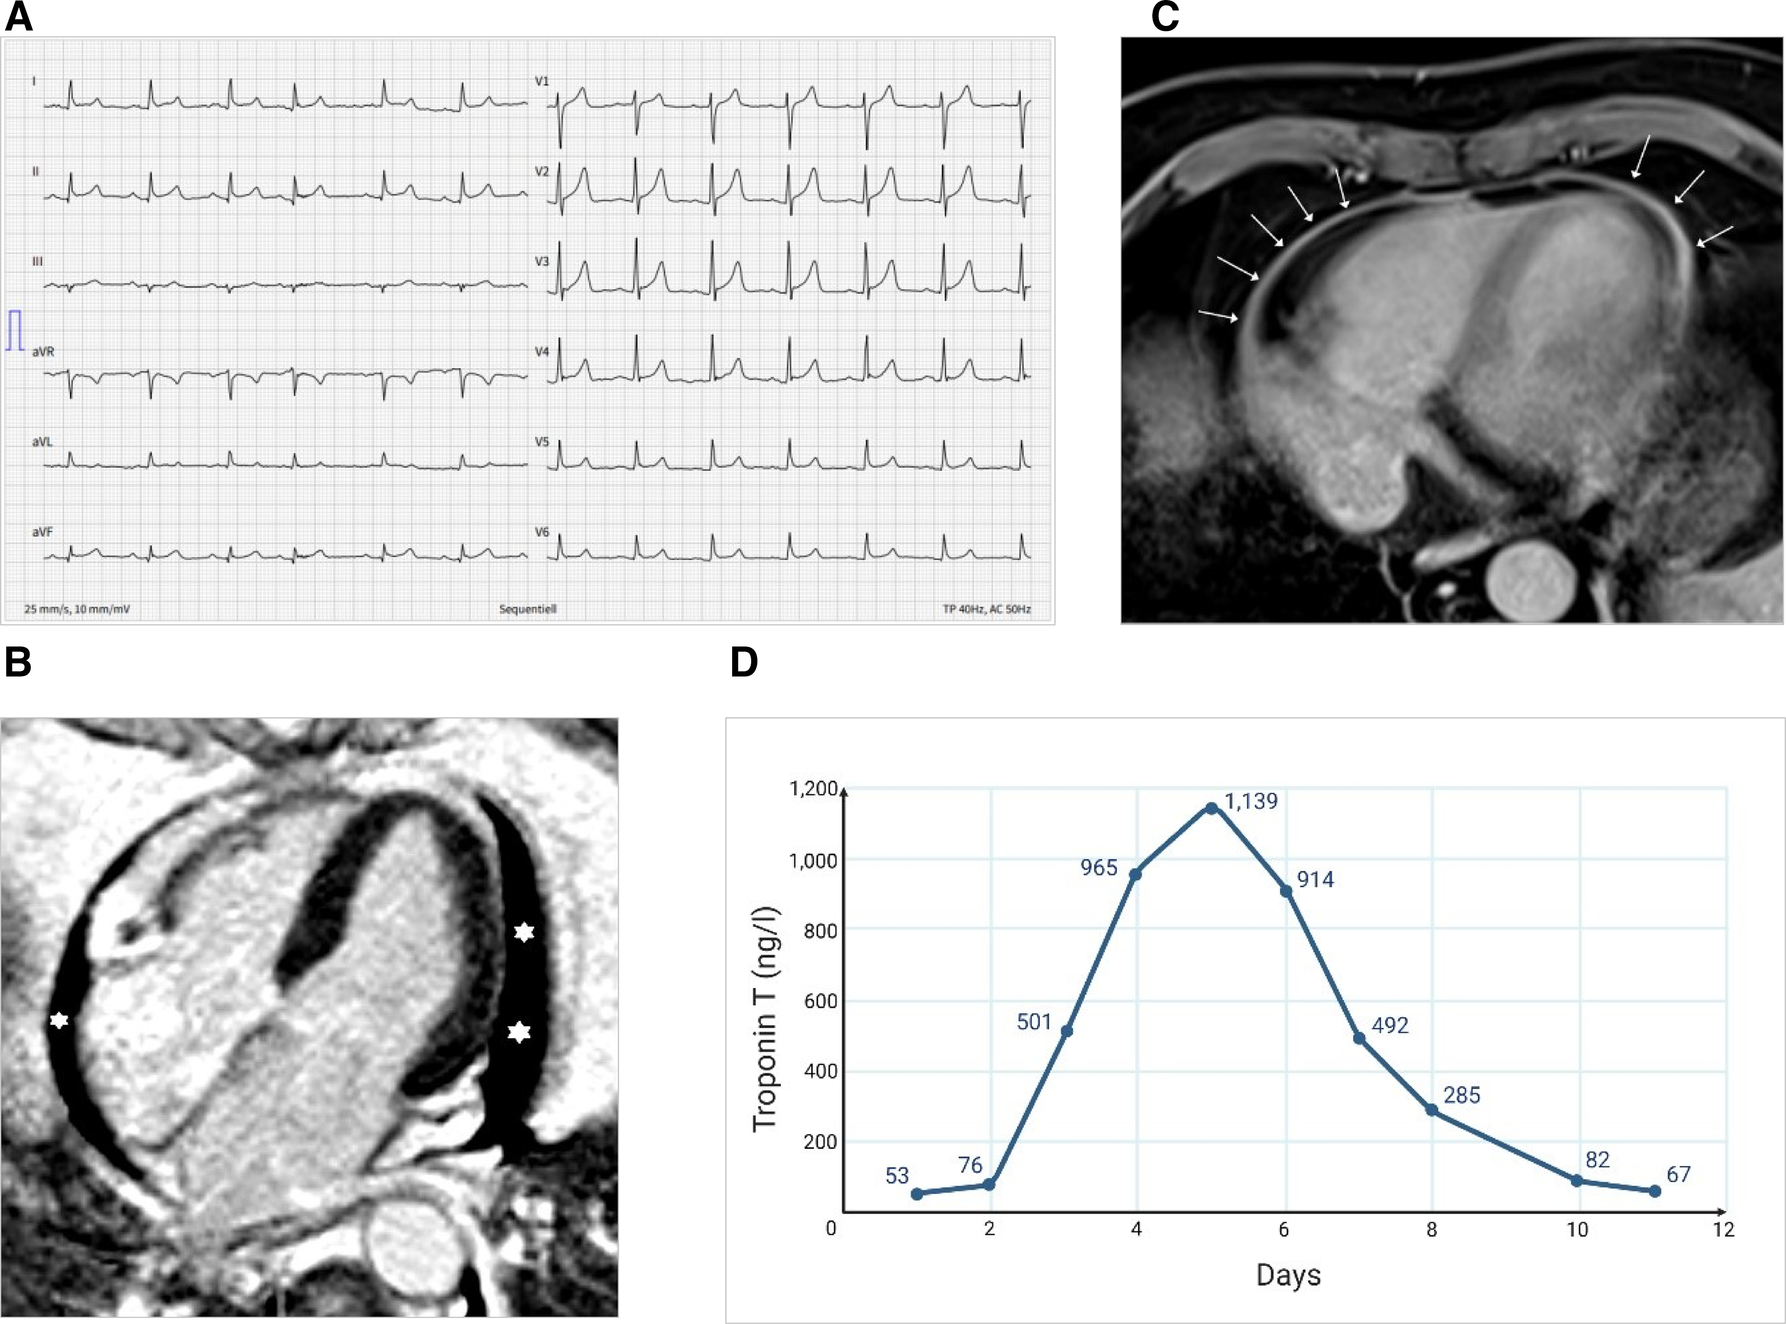

On admission, he was hemodynamically stable (blood pressure 136/79 mmHg, heart rate 79 bpm), afebrile, and adequately oxygenated (oxygen saturation 99% in ambient air). Besides arterial hypertension, no other cardiovascular risk factors were present. An electrocardiogram (ECG) showed concave ST-elevation and PQ-segment depression in several ECG leads and not related to a single coronary artery (Figure 1A). Initial laboratory tests indicated a mildly elevated high sensitivity Troponin T of 53 ng/L (reference <14 ng/L), and an N-terminal prohormone of brain natriuretic peptide (NTproBNP) of 655 ng/L (reference <124 ng/L). The remaining laboratory values are summarized in Table 1.

Figure 1

Electrocardiographic and imaging findings at admission and course of high-sensitive troponin T. (A) ECG showing diffuse concave ST-elevation (II, aVF, V3-6) and PQ-depression (II, aVF). (B) MRI showing pericardial effusion (asterisks) in the four-chamber view (late enhancement PSIR). (C) MRI showing pericardial enhancement (arrows) (axial T1 DIXON Water only, which is a fat-saturated, non-ECG-triggered). (D) Longitudinal evolution of the high-sensitive troponin T levels during the hospitalization (MRI done on day 3; i.e., troponin 501 ng/L).

Aortic dissection, pulmonary embolism, and type 1 myocardial infarction were ruled out by computed tomography scan and coronary angiography, respectively. A single-vessel coronary artery disease with a non-critical right coronary artery stenosis was identified that was not assumed to be responsible for the acute symptoms. Bedside echocardiography showed a hemodynamically insignificant pericardial effusion with preserved left systolic and right heart function bedside echocardiography. A cardiac magnetic resonance imaging (MRI) performed 2 days after symptom onset confirmed pericardial effusion and showed a circumferential pericardial contrast enhancement compatible with pericarditis; the myocardium showed no late gadolinium enhancement and no edema (Figures 1B,C). However, based on the dynamical rise of troponin levels (peak 1,139 ng/L on day 5), a substantial myocardial injury was present. Combined with the ECG changes and cardiac imaging findings and after ruling out alternative causes, acute mRNA vaccine-related probable myopericarditis was diagnosed. No infections or other medical problems in the weeks prior to the presentation could be identified in the patient's history. A nasopharyngeal swab for respiratory viruses, an autoimmune serology panel, and serological tests for enterovirus and adenovirus antibodies were repeatedly negative. A nasal swab and a negative anti-SARS-CoV-2-Nucleoprotein-IgG/M excluded an acute or previous infection with SARS-CoV-2.